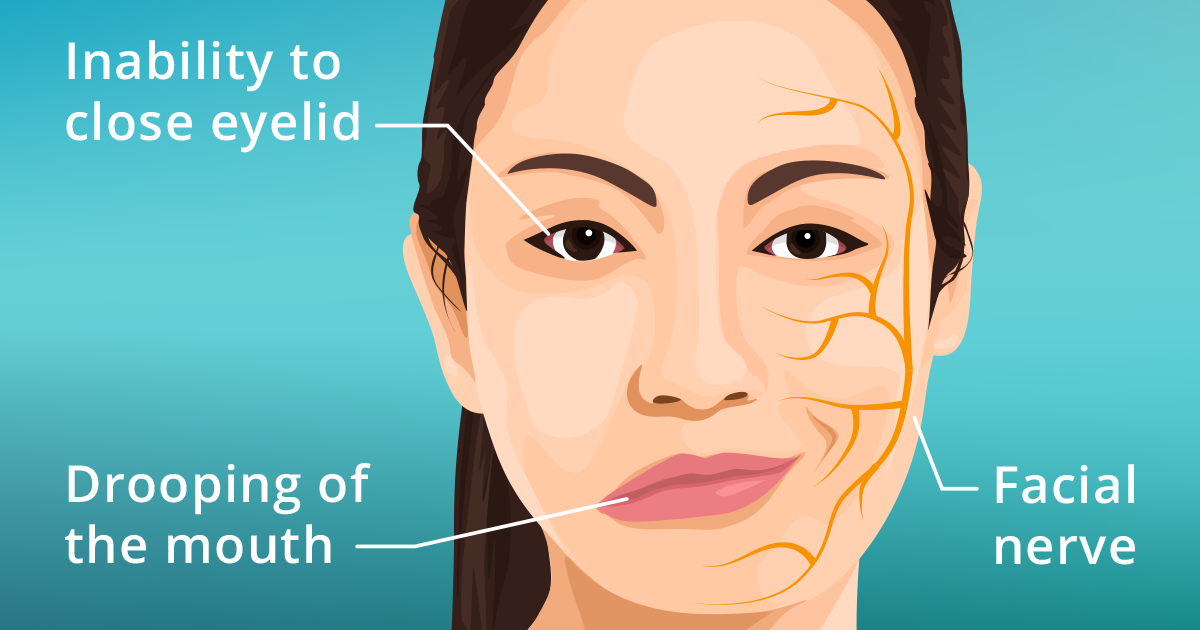

Facial palsy - Muscle weakness on one side of face